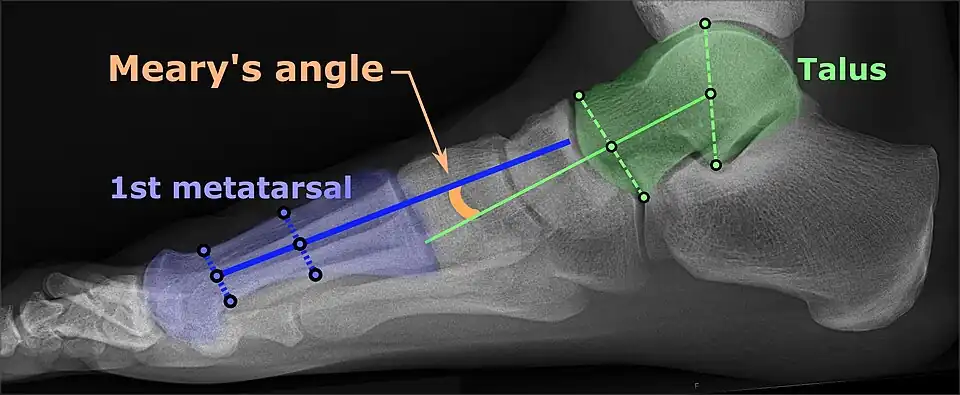

On plain radiography, flat feet can be diagnosed and graded by several measures, the most important in adults being the talonavicular coverage angle, the calcaneal pitch, and the talar-1st metatarsal angle (Meary's angle).[11] The talonavicular coverage angle is abnormally laterally rotated in flat feet.[11] It is normally up to 7 degrees laterally rotated, so a greater rotation indicates flat feet.[11] Radiographies generally need to be taken on weightbearing feet in order to detect misalignment.[12]

Same lateral X-ray showing the measurement of Meary's angle, which is the angle between the long axis of the talus and first metatarsal bone.[11] An angle greater than 4° convex downward is considered a flat foot, 15° - 30° moderate flat foot, and greater than 30° severe flat foot.[11]